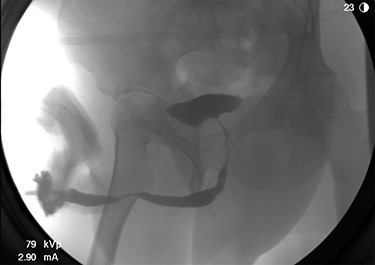

The patient underwent further evaluation with imaging including renal ultrasound, which was normal. Flexible cystourethroscopy demonstrated a circumferential urethral mass concerning for urothelial carcinoma (Fig. 1), which was biopsied with histopathology negative for urothelial carcinoma but positive for amyloid protein deposition. Examination of the external genitalia was unremarkable and there was no palpable induration along the ventral penile shaft. Systemic workup for additional manifestations of amyloidosis was negative. Imaging with retrograde urethrography (RUG) demonstrated an ~2 cm segment of urethral stenosis in the penile urethra (Fig. 2).

RUG demonstrating focal urethral stenosis of the penile urethra during preoperative investigation.